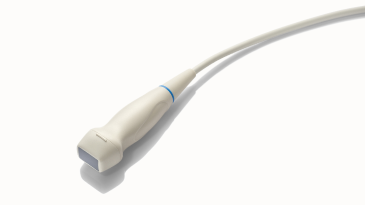

Transducers